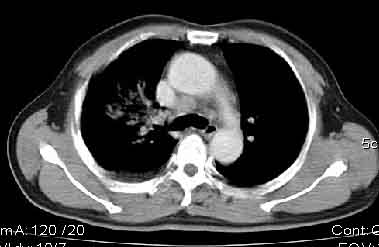

该病例我的诊断意见:右肺上叶周围型肺癌伴纵隔和右肺门淋巴结增大和右肺上叶阻塞性肺炎{病灶周围致密影以近肺门侧明显!}。右侧少量胸腔积液。

一. 1)症状有无发热及慢性过程.2)化验室检查?3)有无tb接触史?二.右肺上叶见片团状影,边界欠清,外侧方见一结节状软组织影,密度欠均匀,内可见低密度坏死区.周围强化明显,肺内见纤维索条影,局部胸膜增厚,但无明确胸膜凹陷.上叶支气管壁增厚,肺门及纵隔淋巴结增大.右侧胸腔少量积液.诊断意见:1右肺上叶慢性感染性疾病(肺tb?)伴肺门,纵隔淋巴结大.右胸少量积液.右肺上叶结节影多为tb球?2右肺上叶周围型肺ca伴肺门,纵隔淋巴结转移待排.右肺上叶炎变(肺门及纵隔淋巴结压迫).右胸少量积液.等待随返结果.

中轴间质增粗可以用癌局部淋巴侵润解释。近肺门侧片影用肺门淋巴结增大解释并压迫支气管引起近端炎症?